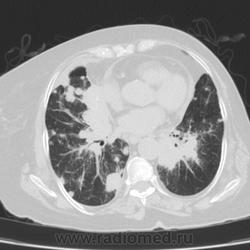

Метастатическое поражение легких.

Пожилая женщина, 76 лет находится на стац.лечении, провели СКТ дообследование.  Сопут- сr левой молочной железы. Такие множественные

поражения  в легких встречаются не часто.

Раннее несколько лет назад оперирована по поводу рака левой молочной железы.

Ну да, неспокойная работа, один тяжелее и  интересней другого. На обзорной рентгенограмме было всё видно прекрасно. Но терапевты направили, а я и не отказалась, чтобы в следующий раз знать- какие они бывают вторичные поражения легких.

Не всё на снимках видно. Многое осталось бы за кадром.